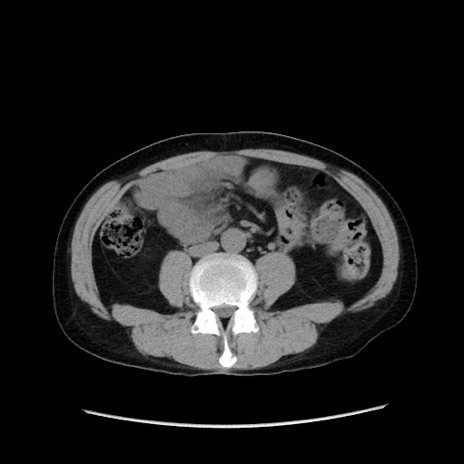

症例37(横断像)

【症例】40歳代 男性

【主訴】腹痛

【現病歴】4時間ほど前に電車に乗車中に臍部上より腹痛出現。徐々に増悪し起立困難となり、救急外来受診。生ものは数日食べていない。今朝お雑煮を食べた。

【身体所見】BT 36.8℃、BP 117/84mmHg、HR 91/min、SpO2 97%、苦悶様、腹部:臍上部広範囲圧痛あり、反跳痛±

【データ】WBC 8100、CRP 0.03